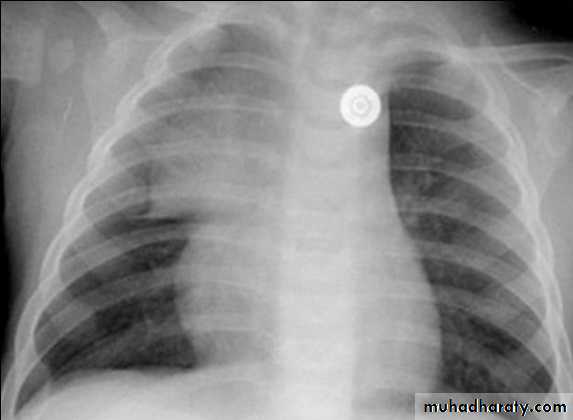

CXR of a neonate ,PA view shows thymus gland (normal finding not a disease ) with indentationsUL: Thymus Indentation sign. UR: Thymic wave sign, Lower: Thymic Sail sign

normal chest XR of the infant( normal thymus gland) Sail sign